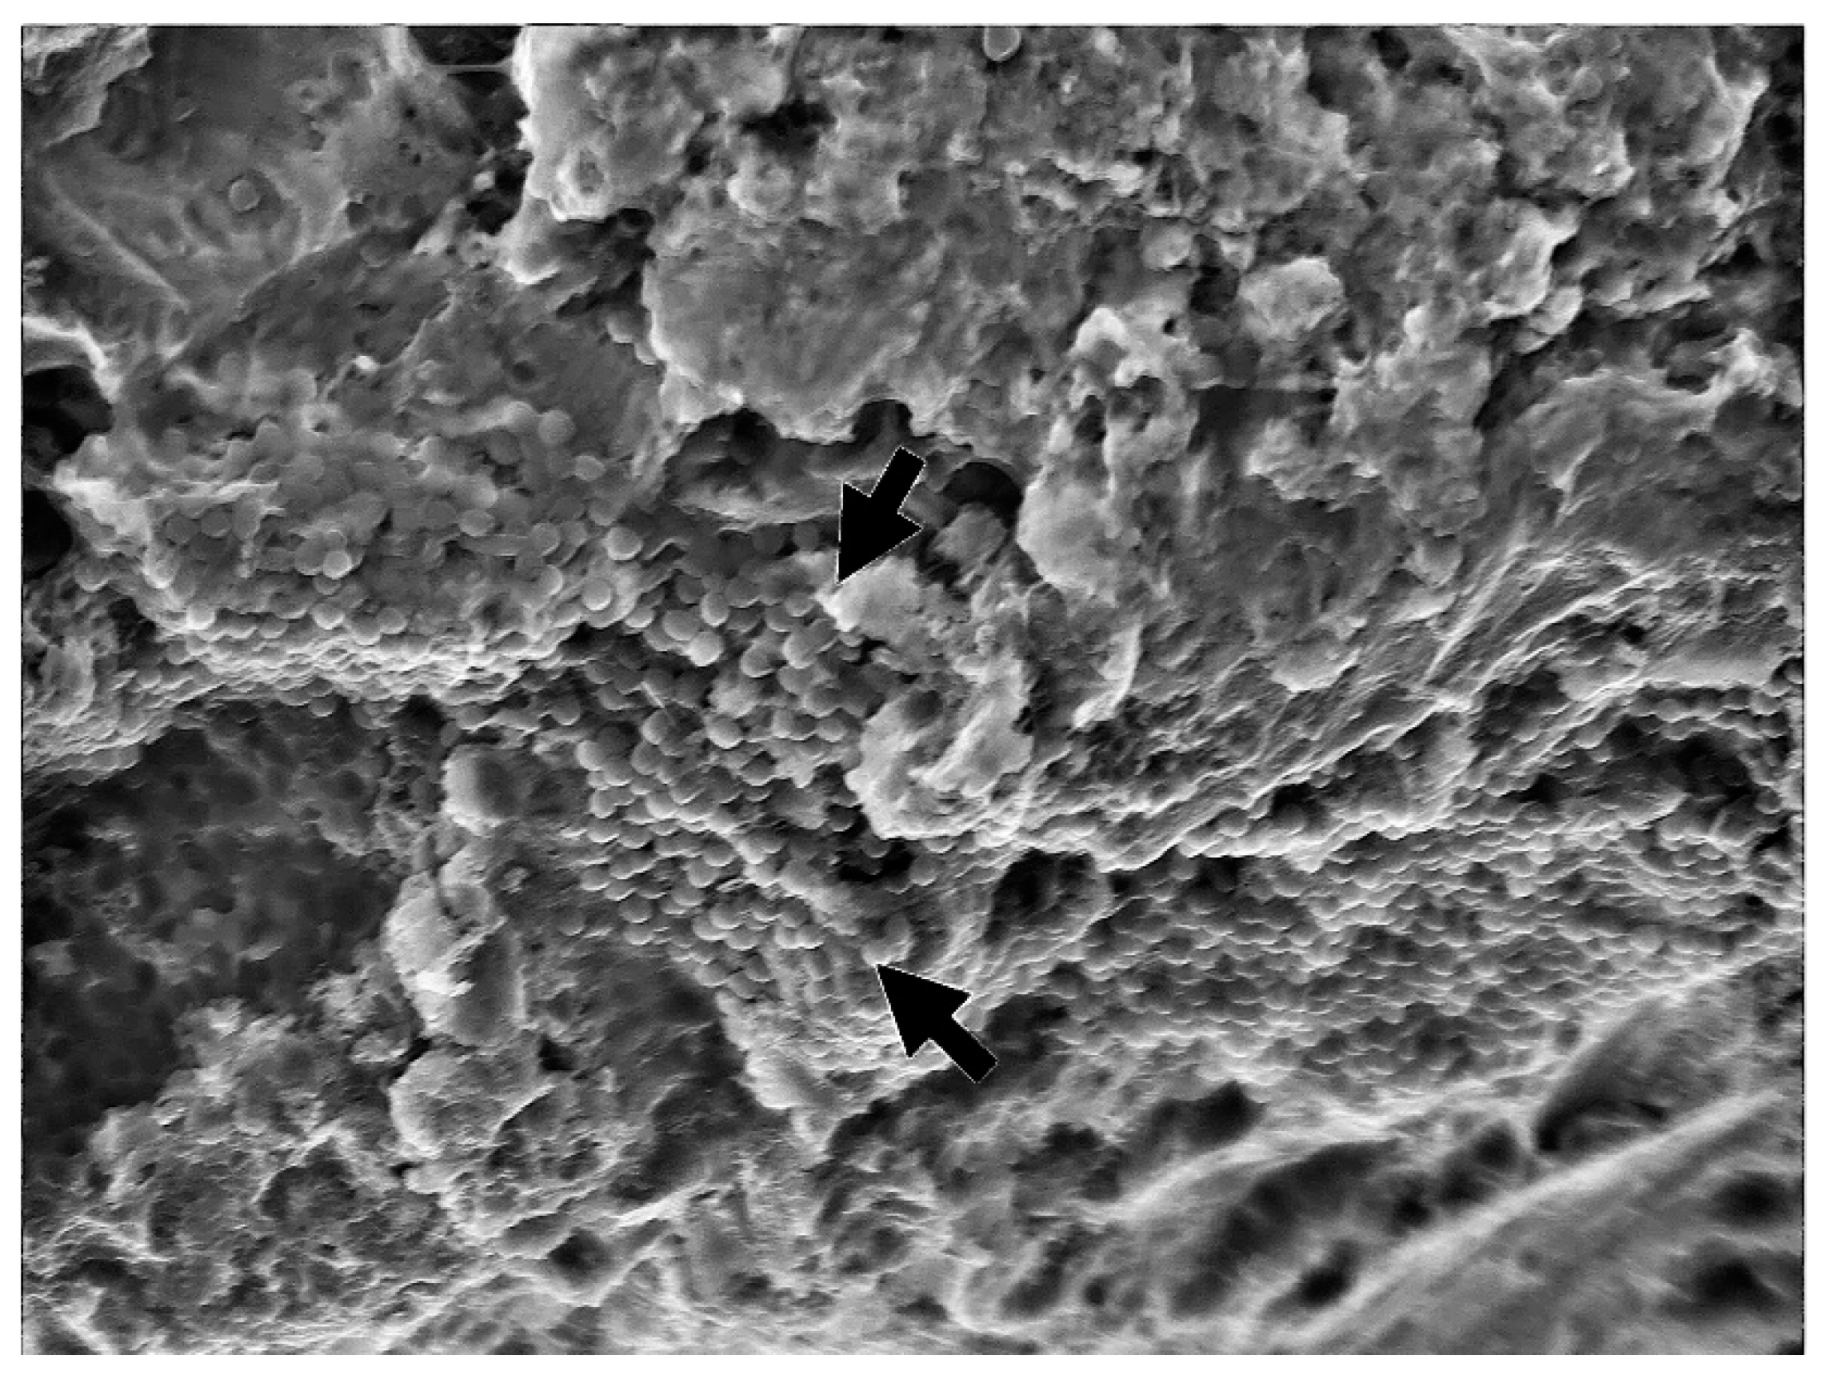

- Leelanarathiwat, K.; Katsuta, Y.; Katsuragi, H.; Watanabe, F. Antibacterial activity of blue high-power light-emitting diode-activated flavin mononucleotide against Staphylococcus aureus biofilm on a sandblasted and etched surface. Photodiagnosis Photodyn. Ther. 2020, 31, 101855. [Google Scholar] [CrossRef] [PubMed]